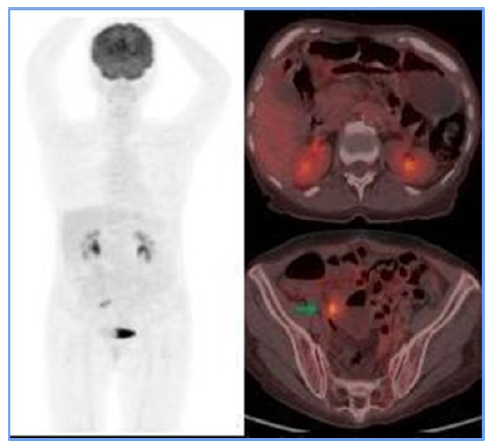

As a result, the treating hematologist recommended a second-line chemotherapy regimen (RICE) for 3 cycles. At the end of these sessions, a follow-up PET scan revealed the resolution of adenopathy in the obturator chain (Figure 3), demonstrating a complete metabolic response. Based on these findings, the patient was declared in remission. Given the favorable evolution, maintenance immunotherapy was initiated with a standard-dose Rituximab regimen for low-grade lymphoma, administered every 2 months for 2 years. As for the writing of this report, the patient has successfully completed 9 cycles and remains in remission.

Figure 3

PET CT scan following the rescue scheme. It presents the resolution of adenopathy in the proper internal iliac chain, which is related to morphological and metabolic responses to medical treatment.

For staging, PET-CT (F18-FDG) is a crucial tool. Initially, it allowed for documentation of both nodal and extranodal involvement, establishing tumor viability and aiding in follow-up and evaluation of treatment response. The Deauville 5-point visual scale [7] was used to assess treatment response. In this case, the PET-CT documented persistent disease (Deauville 4), which influenced treatment decisions and led to escalation of the medical management. A subsequent PET-CT (F18-FDG) performed after rescue therapy demonstrated a complete metabolic response at the end of treatment [8].

In the case presented here, the patient showed a favorable response to chemotherapy, achieving complete remission and surviving for two years to date. Lymph node and extranodal involvement, along with immunohistochemical findings, enabled the diagnosis and timely treatment initiation (Figure 1). The partial metabolic response observed in the post-treatment PET (Figure 2) led to the decision to escalate the treatment to second-line RICE chemotherapy. Eventually, a new PET-CT (F18-FDG) post-treatment (Figure 3) confirmed a complete metabolic response.